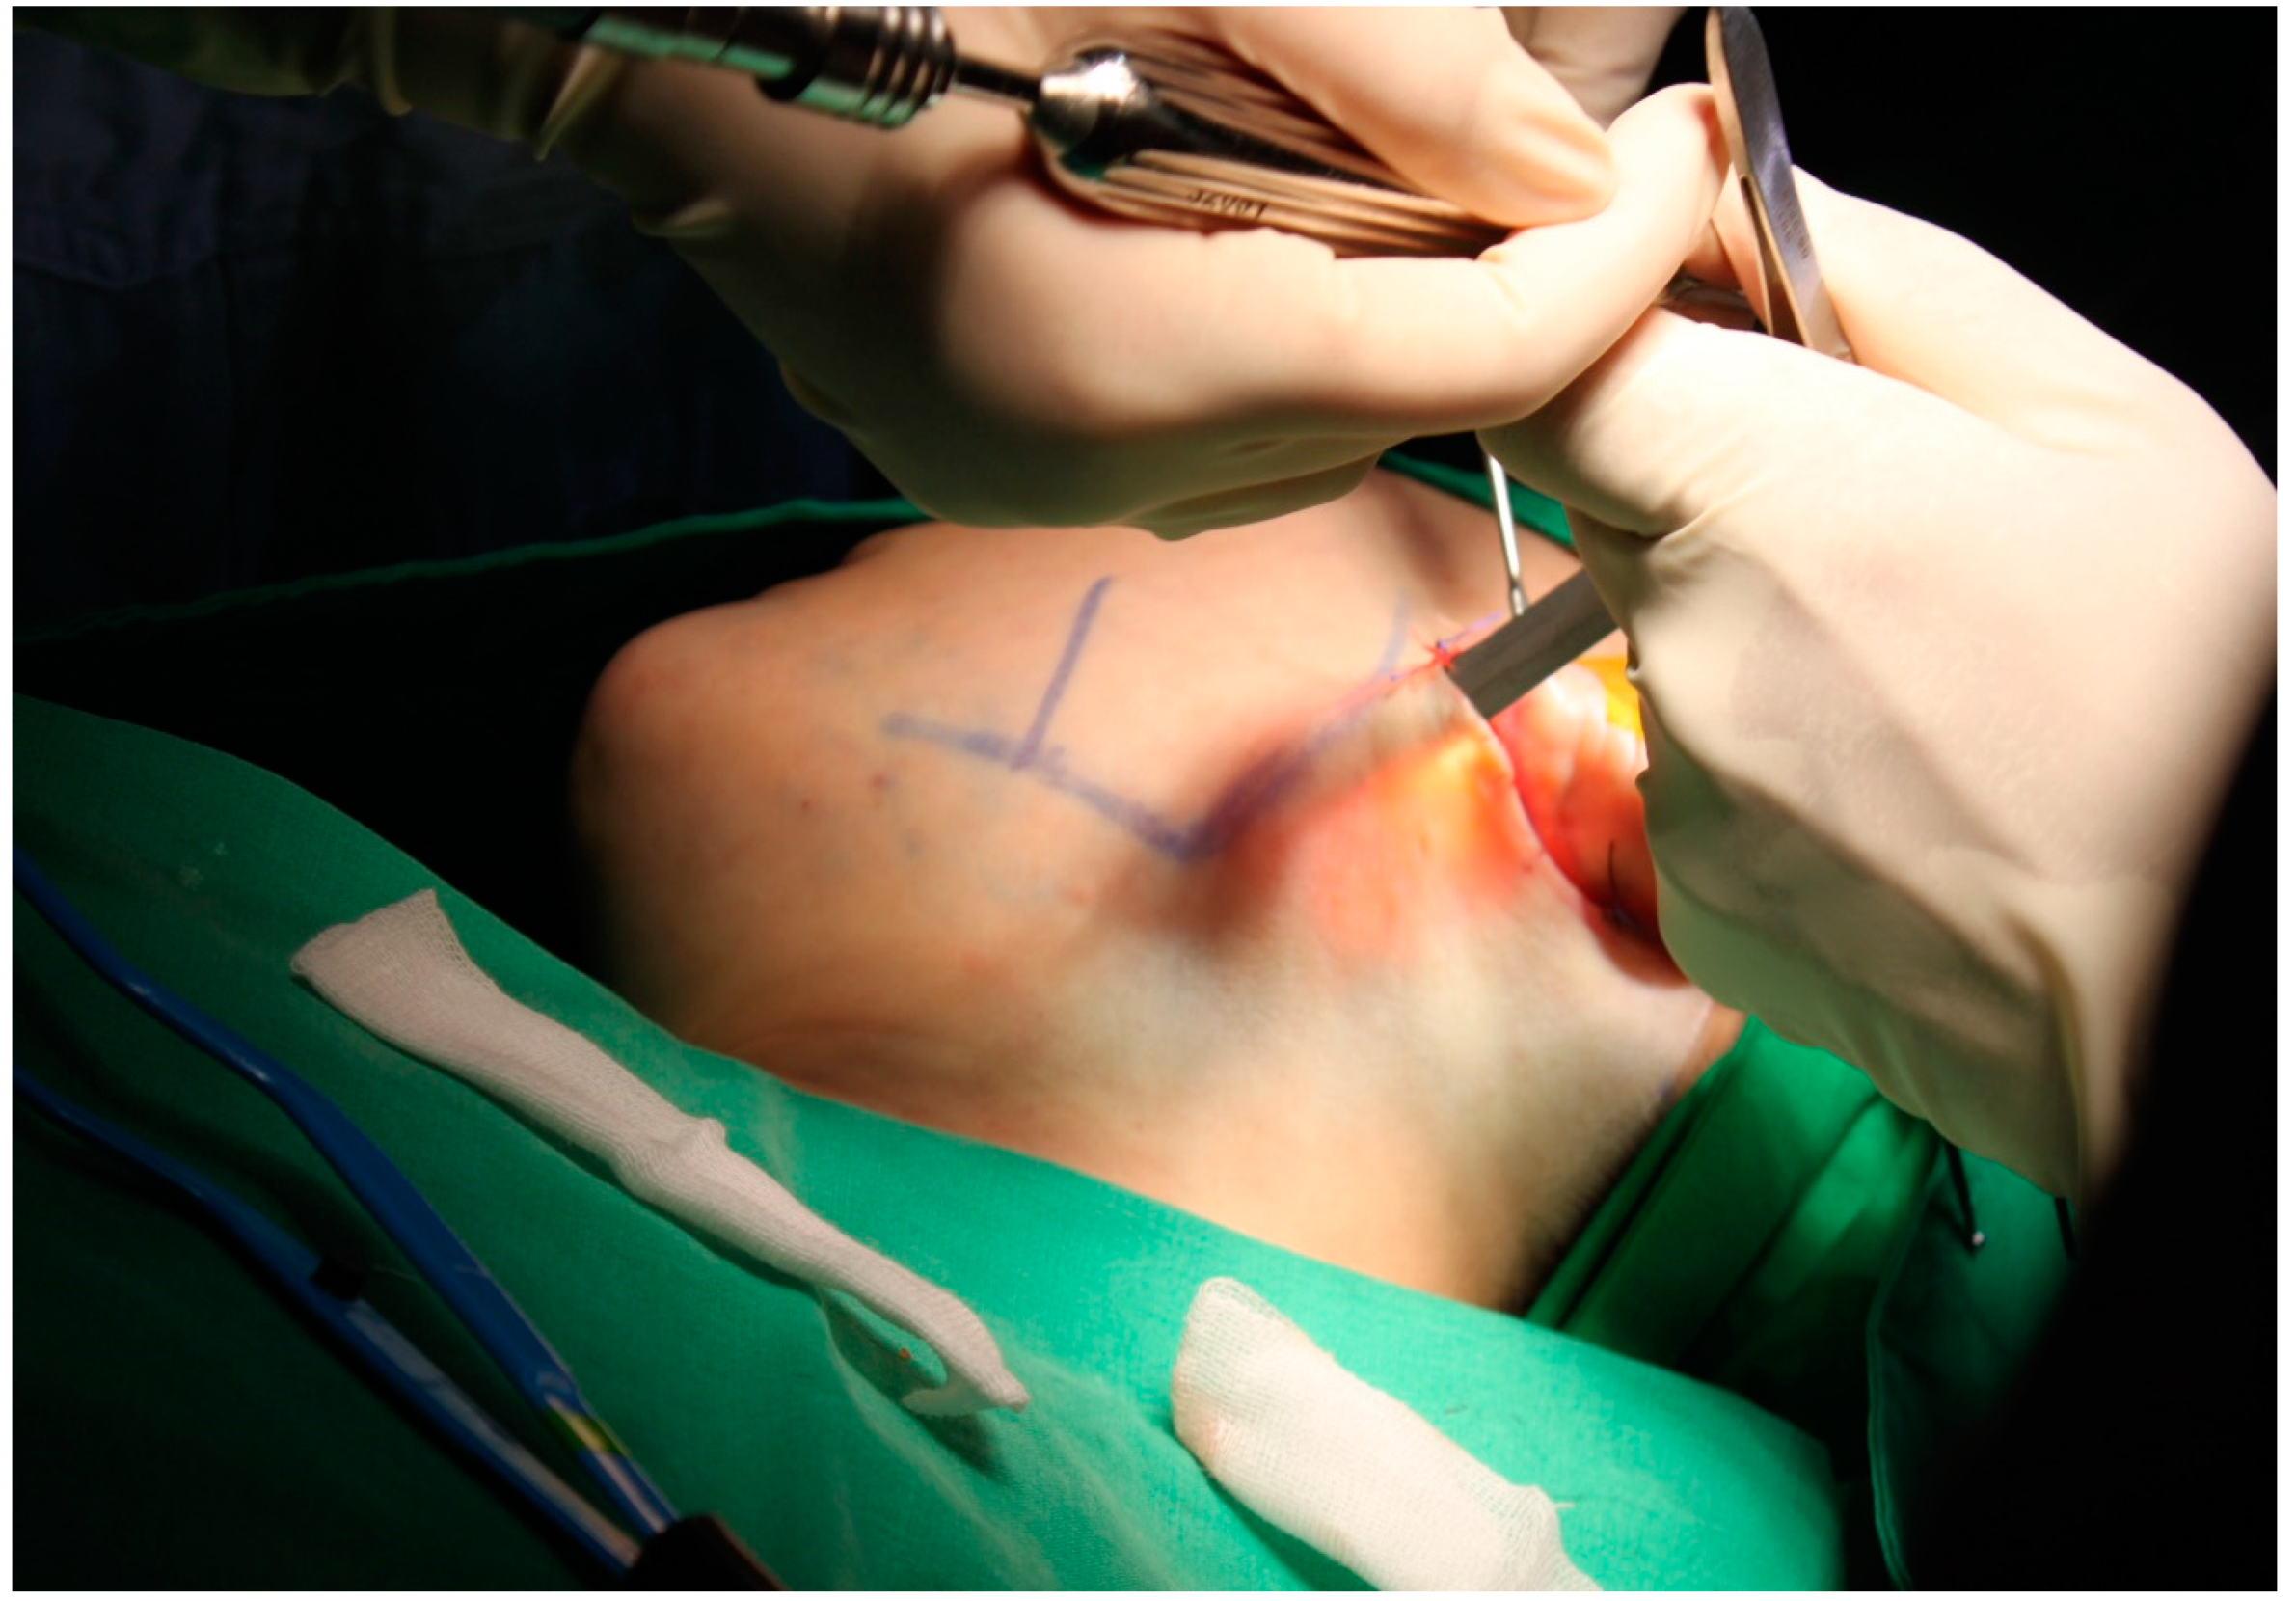

2.1. Surgical Techniques